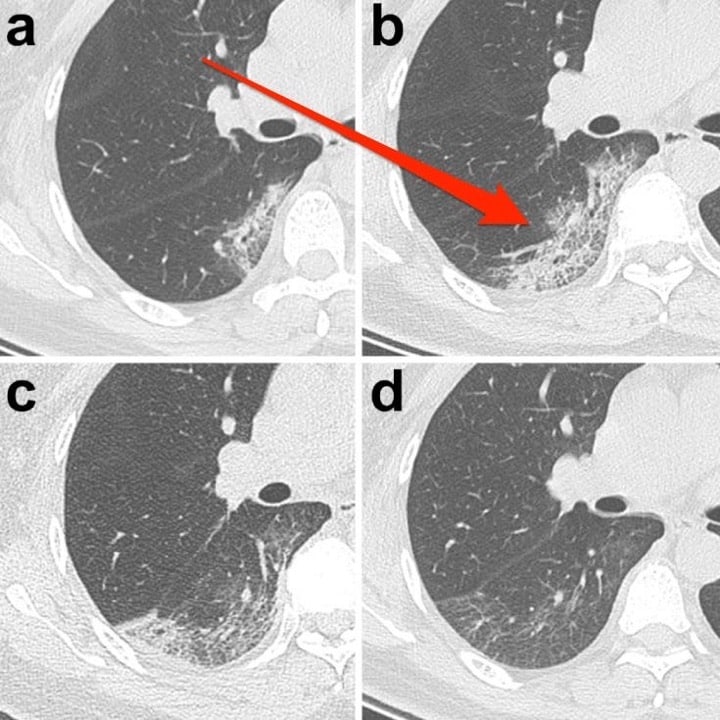

طبق یک مطالعه موردی، یک زن ۳۳ ساله با تب و سرفه پنج روزه، دمای بدن ۳۸.۸ درجه، مشکل تنفسی و تعداد پایین گلبولهای سفید خون، نشانهای از عفونت، به بیمارستانی در لانژو چین مراجعه کرد.در سی تی اسکن اولیه، محققان بیمارستان دانشگاه لانژو «کدورت شیشه مات» را در گوشه پایین ریههای وی شناسایی کردند.به این بیمار اینترفرون، پروتئینی برای درمان عفونتهای ویروسی، تجویز شد اما سه روز بعد (و بعد از درمان او) علائم بارزتر شدند. همین اتفاق در بیماران SARS نیز رخ داده است. «اگر از این شیوع اطلاع نداشتیم با مشاهده اسکن تشخیص پنومونی میدادیم، زیرا این شایع ترین چیزی است که میبینیم.»«ذات الریه معمولاً به سرعت پیشرفت نمیکند»، بنابراین این مورد منتفی است.اسکن ریه کرونایی یک خانم ۲۷ ساله که در ووهان کار میکرد، یک «هاله شیشه مات» را نشان داد؛ لکههای سفیدی که ندول کوچکی را احاطه کردهاند.

«هاله شیشه مات» میتواند یکی از ویژگیهای متمایز عفونتهای ویروسی و پنومونی باشد.«هاله شیشه مات» میتواند یکی از ویژگیهای متمایز عفونتهای ویروسی و پنومونی باشد.محققان دانشگاه پزشکی آنهویی در هفی، چین این زن را پس از بستری شدن در اثر تب و سرفه مورد بررسی قرار دادند. بیمار اختلال تنفسی نیز داشت. محققان گفتند: «هاله شیشه مات» میتواند یکی از ویژگیهای متمایز عفونتهای ویروسی و پنومونی باشد.پس از چهار روز بستری در بیمارستان، ندول ریه راست بیمار رشد کرده بود.برخی از بیماران «الگوی انتشار پیشرونده» را نشان میدهند که به خطوط کم درون کدورت شیشه مات اشاره دارد.